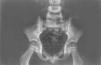

A la semana del ingreso persistía el dolor en cadera derecha aunque había desaparecido la fiebre y mejorado llamativamente su estado general. Se repitió la radiografía simple de caderas encontrándose una lesión osteolítica en rama isquiopubiana derecha (fig. 1); en la gammagrafía ósea con 99Tc se vio hipercaptación en la mitad inferior del hueso ilíaco derecho (fig. 2). Ante los hallazgos se continuó con cefotaxima intravenosa durante 21 días y posteriormente con cefixima oral (8 mg/kg/día) durante 2 semanas más; además se pauta tratamiento antiinflamatorio con ibuprofeno. El hemocultivo realizado el sexto día de ingreso fue negativo.

Figura 1. Radiología simple de caderas con lesión osteolítica en rama isquiopubiana derecha.